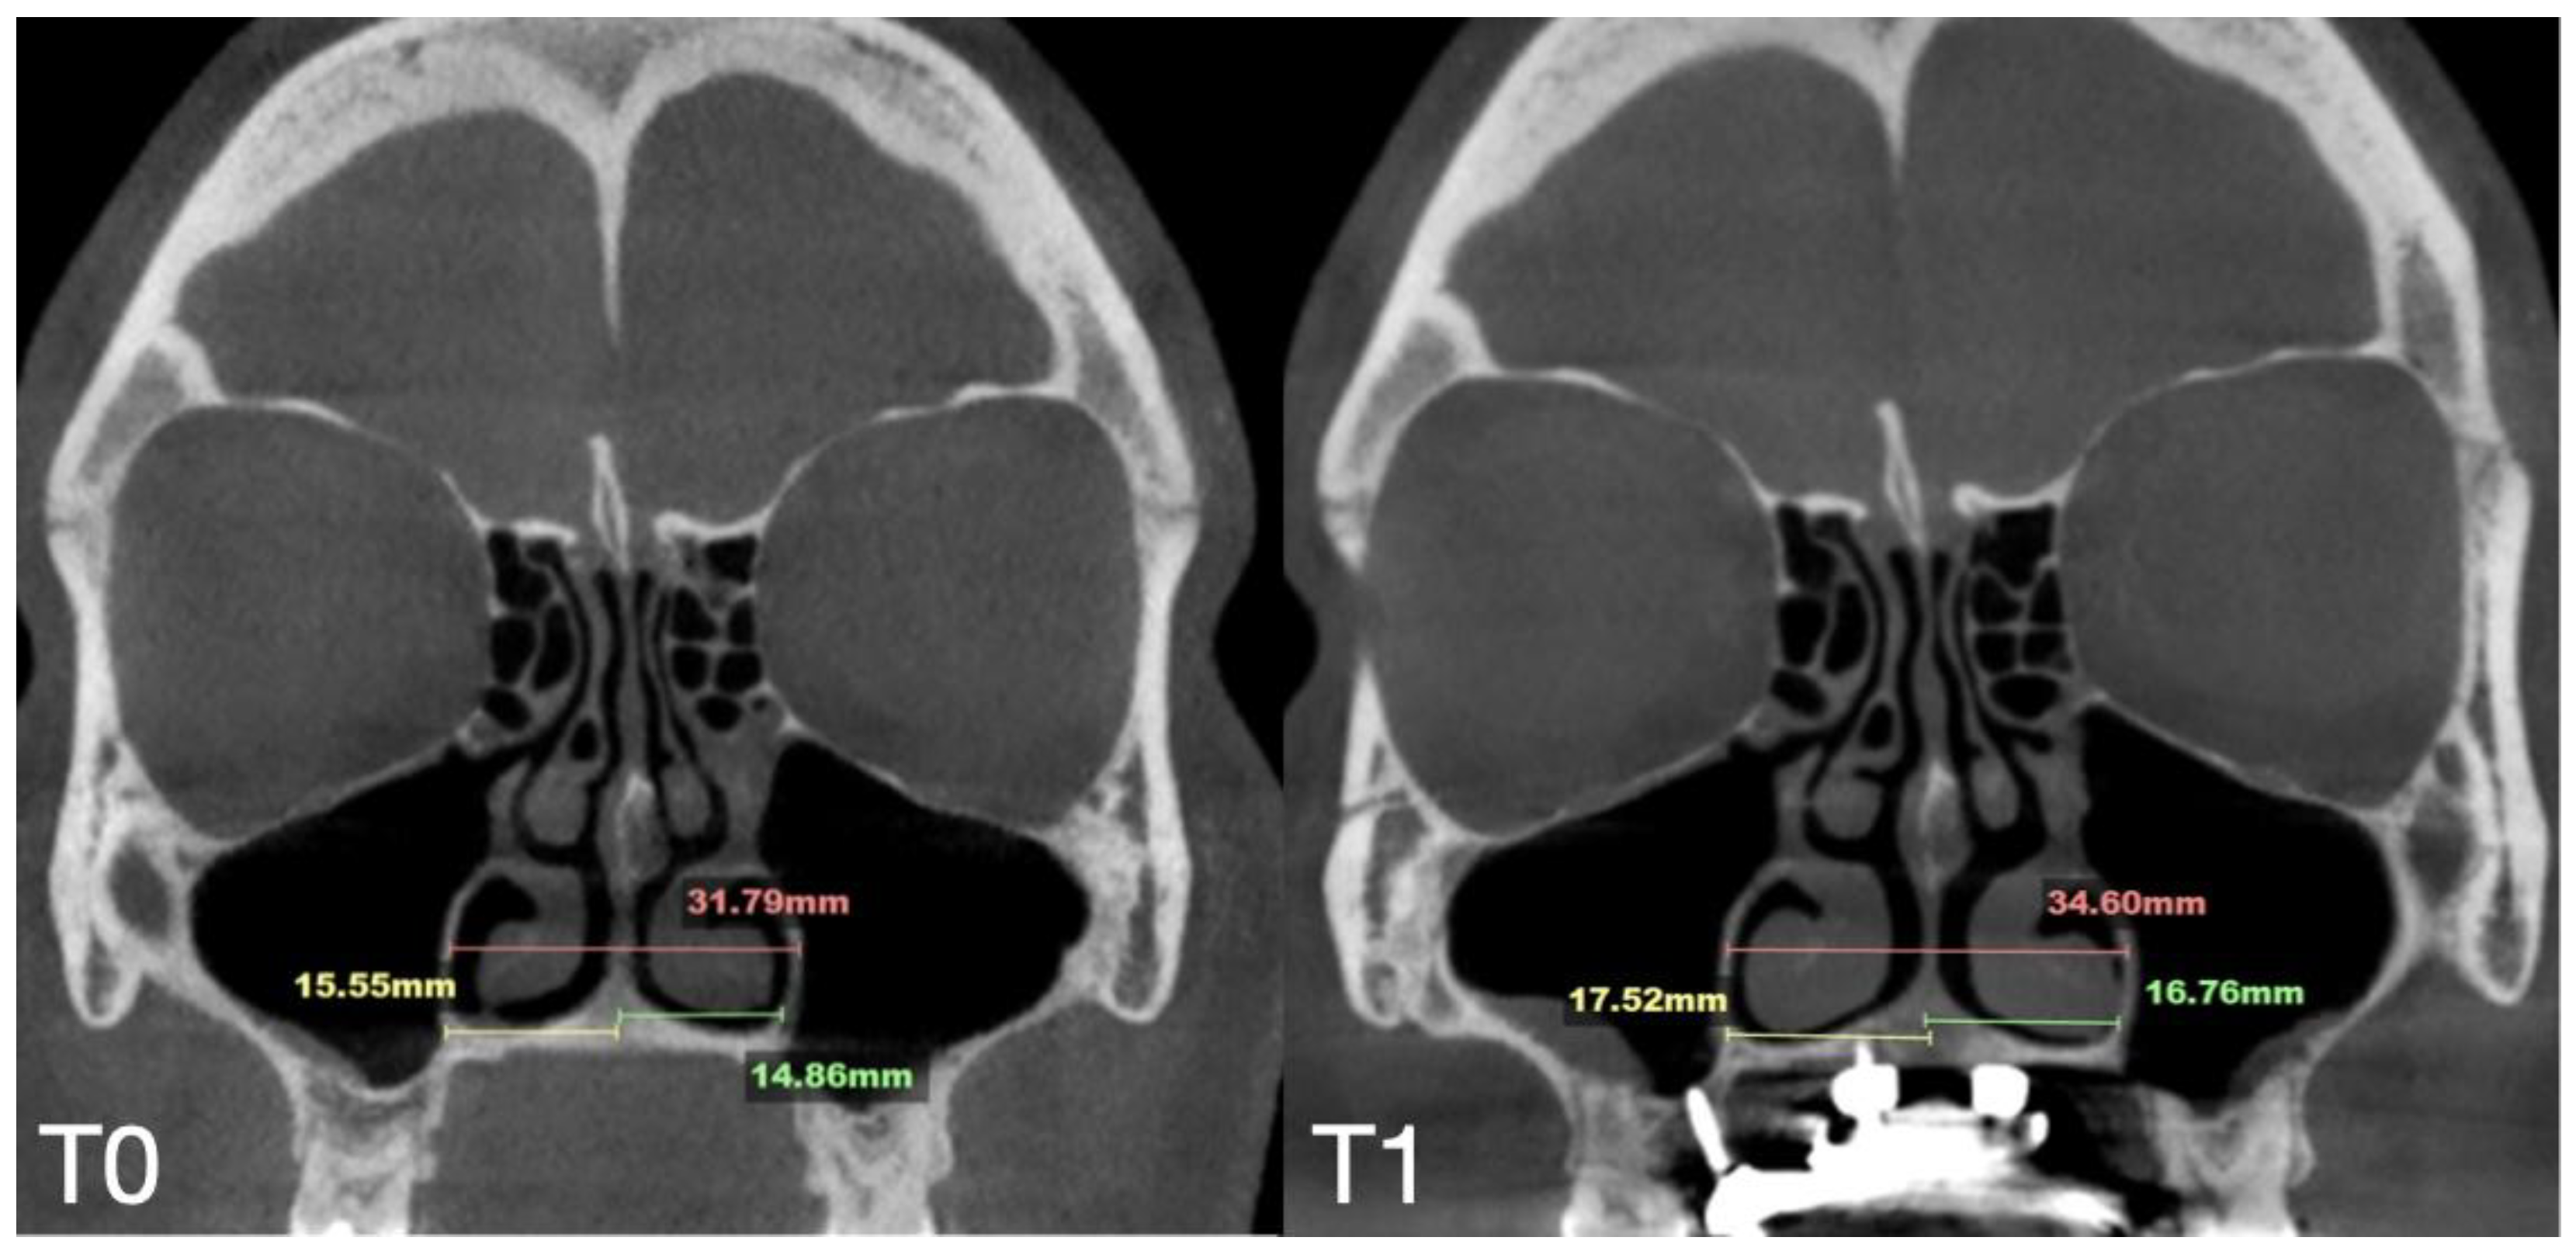

| Case B | 30.61 | 34.41 | 34.97 | 59.73 | 63.47 | 60.56 | 31.79 | 34.6 | 35.35 | 29.18 | 31.38 | 34.59 | 5.7 |